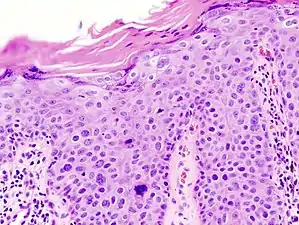

Characteristics

Histopathologically, the epidermis in SCC in situ (Bowen’s disease) will show hyperkeratosis and parakeratosis. There will also be marked acanthosis with elongation and thickening of the rete ridges. These changes will overly keratinocytic cells which are often highly atypical and may in fact have a more unusual appearance than invasive SCC. The atypia spans the full thickness of the epidermis, with the keratinocytes demonstrating intense mitotic activity, pleomorphism, and greatly enlarged nuclei. They will also show a loss of maturity and polarity, giving the epidermis a disordered or “windblown” appearance.

Two types of multinucleated cells may be seen: the first will present as a multinucleated giant cell, and the second will appear as a dyskeratotic cell engulfed in the cytoplasm of a keratinocyte. Occasionally, cells of the upper epidermis will undergo vacuolization, demonstrating an abundant and strongly eosinophilic cytoplasm. There may be a mild to moderate lymphohistiocytic infiltrate detected in the upper dermis.[33]

In situ disease

Bowen's disease is essentially equivalent to and used interchangeably with SCC in situ, when not having invaded through the basement membrane.[33] Depending on source, it is classified as precancerous[34] or SCC in situ (technically cancerous but non-invasive).[35][36] In SCC in situ (Bowen's disease), atypical squamous cells proliferate through the whole thickness of the epidermis.[33] The entire tumor is confined to the epidermis and does not invade into the dermis.[33] The cells are often highly atypical under the microscope, and may in fact look more unusual than the cells of some invasive squamous cell carcinomas.[33]